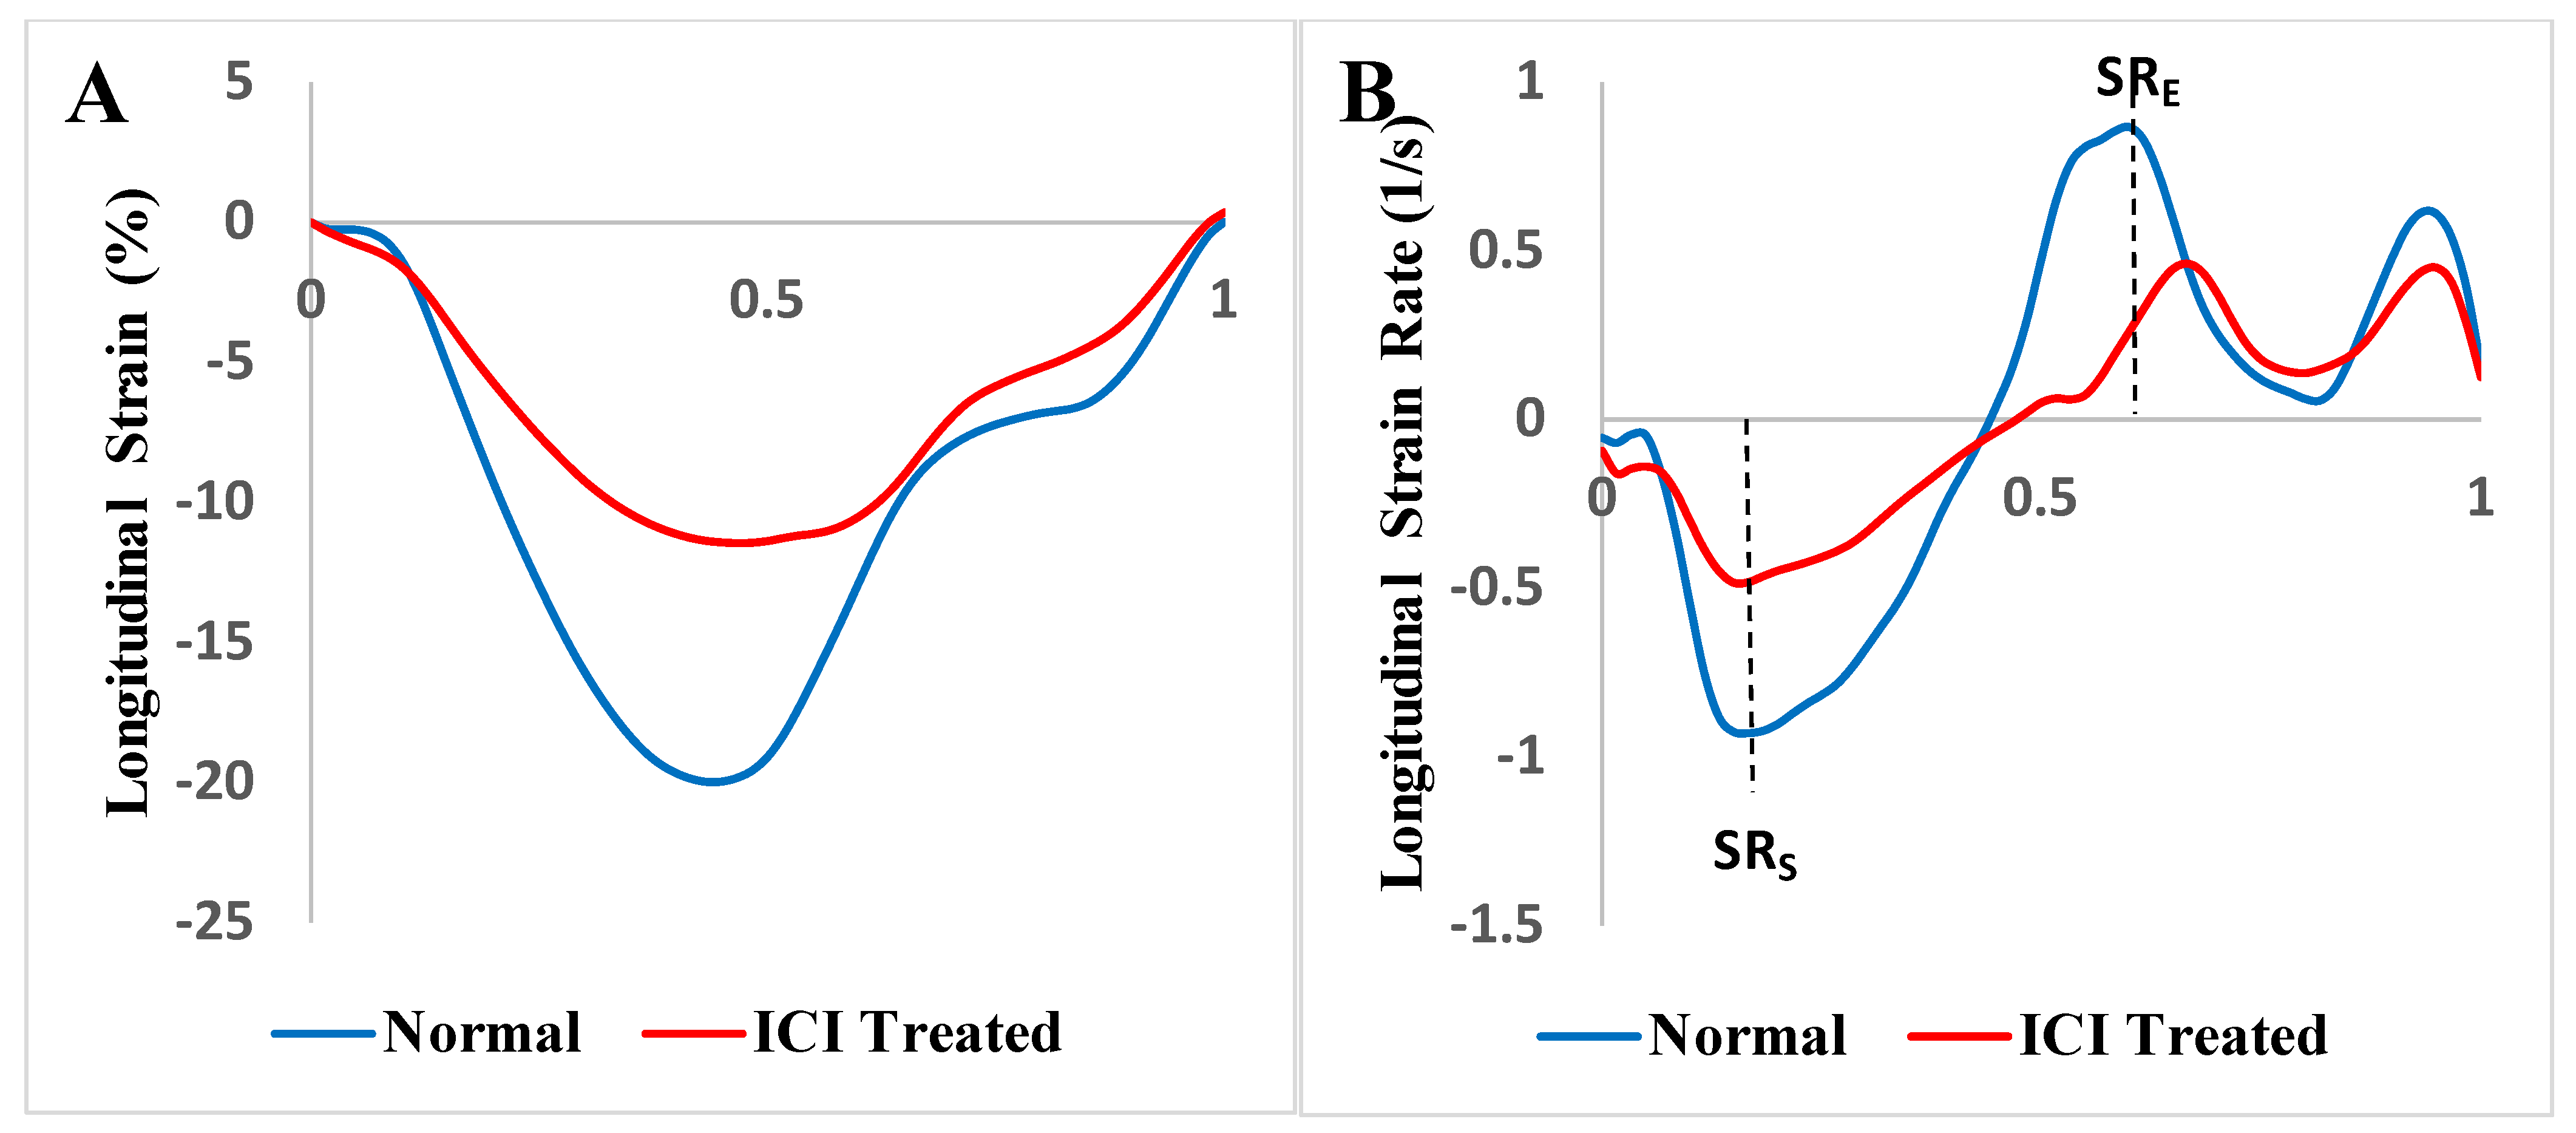

2.3. Strain and Strain Rate Analysis

3.6. Echocardiographic Characteristics

3.8. Comparison of Echocardiography vs. Cardiac Magnetic Resonance Imaging-Based Strains